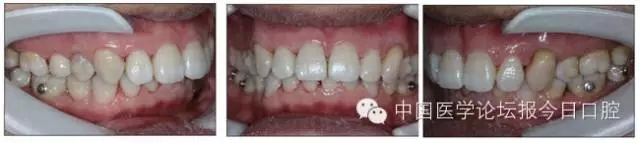

口內(nèi)情況:恒牙列,24、34、44缺失,磨牙Ⅲ類關(guān)系,上牙列散隙,上前牙扇形漂移。前牙深覆(牙合)、深覆蓋。口腔衛(wèi)生較差,11與12間牙齦乳頭紅腫,多個(gè)牙探診有牙周袋形成,11松動Ⅰ度,余切牙松動(-),患者面像及口內(nèi)像如圖1、2所示。

圖2 治療前口內(nèi)像